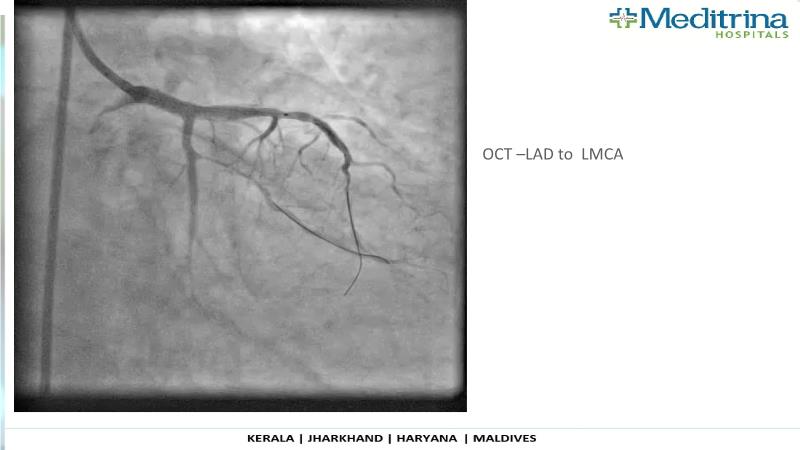

- To define the use of OCT in PCI of complex coronary lesions